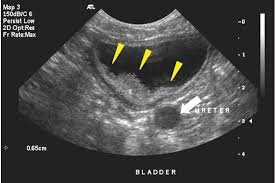

Such ruptures usually lead to sudden internal bleeding, which causes weakness (due to low blood pressure and anemia) and. Many cancer symptoms in dogs are subtle and can be caused by another condition, but if you notice any of the following potential dog cancer warning signs, it's a good idea to talk to your vet. There are two types of bladder cancer in dogs transitional cell carcinoma (tcc) and urothelial cancer (uc). Bladder cancer is much more common in dogs than cats, but tcc only accounts for less than 1% of all reported cancers in dogs. In the urinary system, the bladder is affected with cancer most commonly.

Cancer of the urinary tract in dogs can affect the kidneys, ureters, urinary bladder, prostate, or urethra. Depending on the stage of the cancer, a blockage may have formed in the bladder causing all functions of the bladder to cease. They will talk you through the various options, depending on the type of cancer your dog has. Some of the signs that it's time to say goodbye to a dog with cancer include: The stages of dog cancer staging of cancer helps your veterinarian identify if the cancer has spread to other locations in the body, which can change both the prognosis and appropriate treatment plan. A painful abdomen can be detected by palpating, with flat fingertips, towards the middle of the dog's belly. For example, if we exert gentle back pressure on a standing dog and this is a sore area, sitting quickly may be due to pain. Bladder cancer in dogs can be somewhat tricky to diagnose since the most common symptoms of the disease mimic those of other urinary tract conditions such as stones or infections. If your dog is struggling to pass urine, humane euthanasia should be considered to alleviate current pain and prevent future suffering. Many cancer symptoms in dogs are subtle and can be caused by another condition, but if you notice any of the following potential dog cancer warning signs, it's a good idea to talk to your vet. If the diagnosis of cancer is correct, then one of the tumors may burst. Luckily, when it comes to bladder cancer, researchers have developed a test, called the cadet braf mutation assay, that can help owners get an accurate diagnosis before it is too late. Often, the signs are very similar to urinary tract infections, and these usually take the form of such things such as frequent urination, incontinence, and traces of blood in their urine.

Luckily, when it comes to bladder cancer, researchers have developed a test, called the cadet braf mutation assay, that can help owners get an accurate diagnosis before it is too late. Canine bladder tumors, most commonly transitional cell carcinoma (tcc) or urethelial carcinoma, have long been a frustrating disease to diagnose. Bladder cancer is much more common in dogs than cats, but tcc only accounts for less than 1% of all reported cancers in dogs. Knowing the symptoms of bladder cancer can help you to detect the disease early, should you think your dog has it. There are two types of bladder cancer in dogs transitional cell carcinoma (tcc) and urothelial cancer (uc). What to expect — faqs what are the symptoms of late stage bladder cancer in dogs? Generally, it's hardest to treat the cancer at this point. If your pup has developed bladder cancer you may notice one or more of the following symptoms: That's as many as i can think of right now. Options may include surgical treatment, combination therapy of surgery and chemotherapy, radiation. Often, the signs are very similar to urinary tract infections, and these usually take the form of such things such as frequent urination, incontinence, and traces of blood in their urine. Tcc can occur in any breed but is most common in shetland sheepdogs, scottish terriers, wirehair fox terriers, west highland terriers, and beagles. There is a new, simple diagnostic …